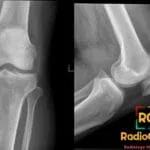

- Radiology Cases: Images with a to-the-point discussion highlighting the specific diagnostic criteria.

- Radiology Case of the Day Collection: Aunt-Minnie Board Cases for Rapid Review.

- Radiology Spotters: 700+ spot / “Aunt-Minnie” cases divided into sets of 10 each!